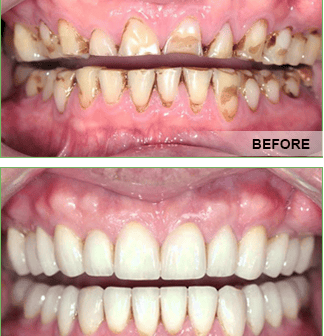

Full Mouth Reconstruction

As the name implies, full mouth reconstruction refers to rebuilding and/or replacing all of the teeth in a patient’s mouth. Full mouth reconstructions combine esthetics with the science of restorative dentistry to improve the health, function, and beauty of the mouth.

Who Requires a Full Mouth Reconstruction?

There are a number of people who have dental problems throughout their mouths that must be treated comprehensively with a vision of a final result that improves both function and esthetics. These patients may exhibit multiple missing teeth, numerous teeth with large fillings that are failing or exhibiting decay, cracked or broken teeth, or badly worn teeth due to bruxism (teeth grinding) or other habits.

There is also a group of patients who were born with conditions such as Ectodermal Dysplasia, Ameliogenesis, or Dentinogenisis Imperfecta that will need extensive restoration of their teeth. These patients may be candidates for a full mouth reconstruction.

Treatment Options for a Full Reconstruction

In general, any dental treatment that affects all teeth in the mouth is called full mouth reconstruction or full mouth rehabilitation. Some treatment options for oral cancer may require the patient to undergo a unique type of full mouth reconstruction that not only involves the replacement of missing teeth, but potentially restoration of missing structures of the oral cavity.

The treatments can include onlays, crowns, bridges, veneers, dental implants, and/or dentures that will essentially provide not only a "smile makeover", but improved chewing efficiency for the patient. In some patients, other specialties will orthodontics may also be employed to facilitate the best possible outcome.